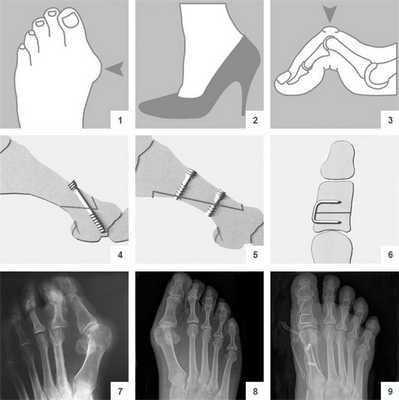

Первая стадия hallux valgus чаще всего проявляется только изменениями на 1 луче стопы (первой плюсневой кости и 1 пальце). На этой стадии происходит небольшое отклонение 1 плюсневой кости кнутри (межплюсневый угол менее 13 градусов) и соответствующим отклонением 1 пальца кнаружи (угол вальгуса менее 25 градусов). На первой стадии пациентов беспокоит формирование "косточки" по внутренней поверхности головки 1 плюсневой кости, которое может приводить к бурситу- воспалению подкожной синовиальной сумки. На этой стадии пациенты чаще хотят просто избавиться от косточки, и не готовы к радикальному хирургическому лечению, так как после него следует длительный реабилитационный период. По сути это косметическое вмешательство, которое состоит из резекции костного экзостоза в обалсти головки 1 плюсневой кости, бурсэктомии, пластики суставной капсулы.

Клинический пример хирургического вмешательства по поводу халюс вальгус 1 степени у женщины 45 лет, которую в большей степени беспокоил косметический изъян и эпизодическое воспаление подкожной синовиальной сумки при ношении узкой обуви и физической нагрузке.

Так как пациентка была заинтересована в максимально быстрой реабилитации то ей была выполнена резекция костного экзостоза, бурсэктомия и пластика суставной капсулы. Такая операция не сопровождается созданием искусственного перелома 1 плюсневой кости - остеотомией, поэтому не требуется 6-недельный период ношения специальной обуви (ботинки Барука) и переход к обычной обуви возможен уже через 2 недели после операции.

Операция McBride

Наиболее популярна среди всех хирургических вмешательств на мягких тканях стопы. Ее суть заключается в перемещении сухожилия m. adductor halluces на головку I плюсневой кости. Это позволяет сблизить между собой кости плюсны и восстановить нормальный мышечно-сухожильный баланс стопы.

К сожалению, отводящая мышца первого пальца неспособна противодействовать постоянной нагрузке. Именно поэтому частота рецидивов после операции McBride довольно высока. Если человек не устраняет действие провоцирующих факторов - у него вскоре снова развивается Hallux Valgus. Избежать этого помогает ношение ортопедической обуви, отказ от каблуков и тяжелой физической работы.

При ярко выраженных деформациях операцию McBride дополняют остеотомией I плюсневой кости SCARF.

CHEVRON

В ходе операции хирург выполняет V-образую остеотомию. Он перепиливает первую плюсневую кость в области головки, а костные фрагменты соединяет с помощью специальных титановых винтов. Поскольку фиксация очень прочная, в послеоперационном периоде пациент не нуждается в гипсовой иммобилизации.

Отметим, что Chevron-остеотомия эффективна только при незначительной деформации первого пальца стопы. В наше время в ортопедии ее используют все реже. Вместо нее большинство врачей делает Scarf-остеотомию.

SCARF

Z-образная остеотомия Scarf - это золотой стандарт лечения вальгусной деформации. Она позволяет установить головку плюсневой кости под нужным углом. В ходе хирургического вмешательства врачи также убирают деформацию суставной капсулы и меняют направление некоторых сухожилий.

Когда операции Scarf недостаточно - хирурги делают проксимальную клиновидную остеотомию или артродез.